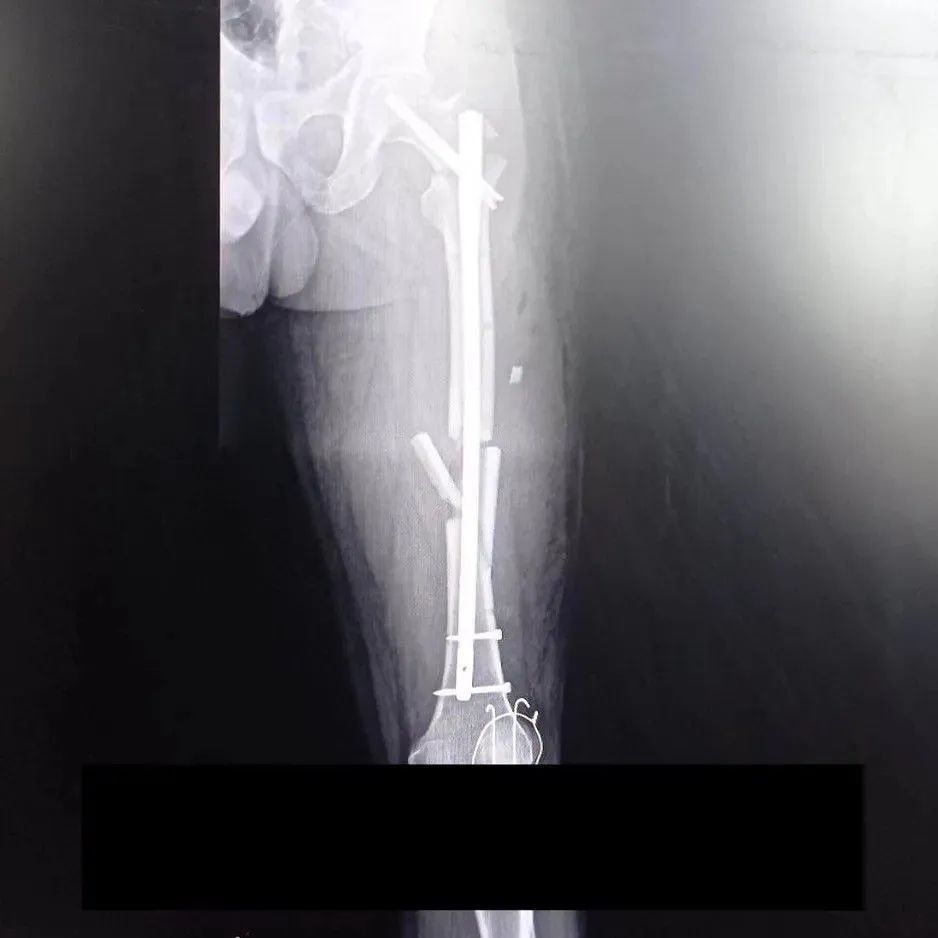

Жена потерпевшего добавила, что его доставили в больницу Тернополя. Там ее не пускали в реанимацию, а также не хотели давать никакой информации о состоянии мужа. У Олега рваные раны обеих рук, сломанный палец, четыре перелома левой ноги, повреждение коленного сустава и два перелома костей.